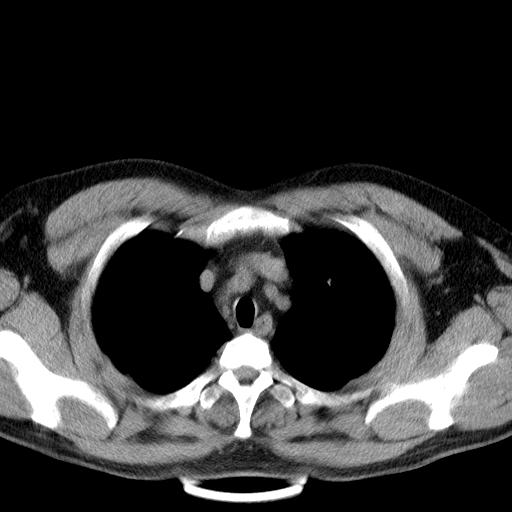

患者男性 35 主因发热咳嗽四天,血象不高,心肺听诊未见异常,无其它病史及传染病接触史。

两肺散在大小不等小结节影,下野较多,纵隔淋巴结增大。考虑:1、慢性血播性肺结核;2、霉菌病?3转移瘤待排。

两肺多发结节,部分病灶边缘不清,且示毛玻璃影。分布特点为沿血管支气管分布。

结合临床考虑;1,炎性肉芽肿性病变;霉菌?过敏性肺炎?2,韦格氏肉芽肿。3,转移瘤。

双肺多发散在结节影,部分边界不清,延支气管分布;纵隔内多发小结节(淋巴结)影...

双肺及胸膜下见多发结节影,最大直径约0.4,内密度均匀,中纵隔腔静脉后见小淋巴结影。